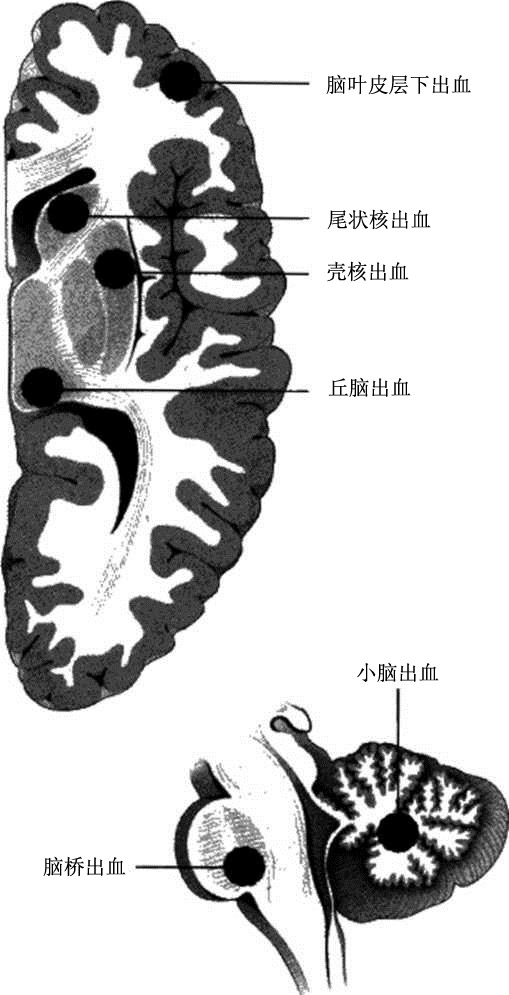

脑出血

图7 大脑的水平切面和脑干的矢状面,可见脑出血的常见部位。

脑出血的最常见原因是髙血压,其部位与高血压性动脉脂质透明样变性相同(图7)。1872年, Charcot和Bouchard首次提出了微动脉瘤的概念,他们认为脑出血是由微动脉瘤破裂引起的。即使患者没有长期高血压病史,突然升高的血压和脑血流量也可引起上述穿通动脉的破裂,从而导致脑出血。而脑血管畸形则可引起任何部位的脑出血;此外,累及蛛网膜下腔和脑皮质内中小动脉和微动脉的脑淀粉样血管病也是脑出血的原因之一。